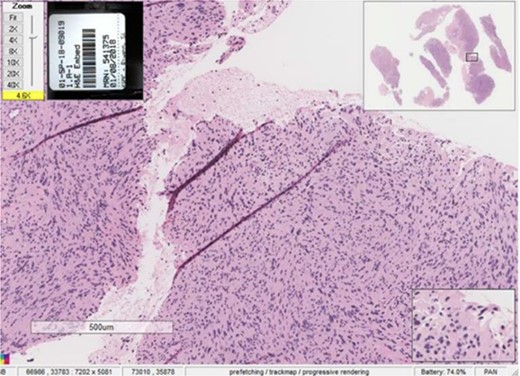

An incisional biopsy under local anesthesia revealed Antoni A and B patterns with hyalinized Verocay bodies among spindle-shaped cells, diagnosing the mass as a schwannoma (Figs 4 and 5).

Histopathological examination showing Antoni A and Antoni B patterns with hyalinized Verocay bodies among spindle-shaped cells.

Close-up view of the histopathological slide confirming the diagnosis of schwannoma.